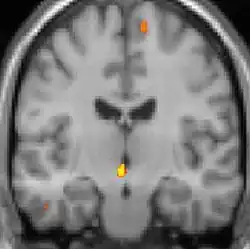

| La tomographie par émission de positons (TEP) montre les zones du cerveau étant activées durant la douleur | ||

Les images par tomographie à émission de positron indiquent les régions du cerveau qui sont activées lors de la douleur, par rapport aux périodes sans douleur. Elles montrent les régions du cerveau qui sont toujours actives durant la douleur en jaune/orange (appelé "matrice-douleur"). La zone au centre (dans les trois vues) est spécifiquement activée uniquement pendant la crise. Les photos sur la ligne du bas (effectuées par VBM) montrent les différences structurelles entre les patients souffrant d'AVF et des personnes saines : seulement une partie de l'hypothalamus est différente[50],[51].